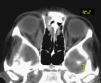

Pruebas complementarias. Hemograma: 12.900 leucocitos/μl (63% neutrófilos); velocidad de sedimentación globular 33mm/h; proteína C reactiva 1,2mg/dl; aldolasa 10,6 U/l (1,0-7,5). El resultado de la bioquímica sanguínea, el sistemático de orina, la enzima conversora de angiotensina, el estudio de hormonas tiroideas, inmunoglobulinas, anticuerpos antitiroideos, antinucleares y anticitoplasma de neutrófilos fueron normales. Prueba de tuberculina, negativa.. Se realizó una TC orbitaria con contraste en el que observa celulitis preseptal interna y miositis aislada del músculo recto interno derecho, sin afectación de los senos cavernosos ni ápex orbitario (Figura 1).

Figura 1. TC orbitaria: engrosamiento y realce difuso del músculo recto interno derecho.